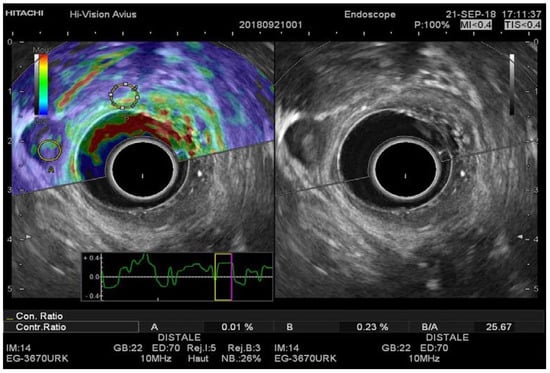

Figure 2. (A) EUS-RTE aspect in a 59-year-old male with pT2 rectal cancer. The tumor was classified as T2 by using the strain ratio (B/A); (B) EUS aspect of the same tumor confirmed by histopathologic examination after surgical resection. RTE, real-time elastography; EUS, flexible endorectal ultrasound.